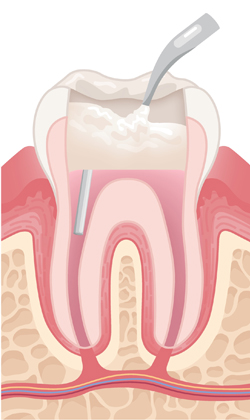

When a tooth is severely damaged or decayed, an infection can form and spread to the nerve tissue and pulp. To repair and save the tooth, a root canal treatment is performed by our endodontist. During the root canal procedure, the infected nerve and pulp are removed and the inside of the tooth is cleaned and sealed.

Some symptoms that can indicate the need for a root canal are persistent pain while chewing or biting, sensitivity to hot or cold, swollen or tender gums, tooth discoloration, chipped or cracked teeth, and pimples on the gums.

A tooth that has had a root canal treatment is not as sturdy as before, due to the removal of a large portion of the pulp. Thus it is common that the root canal treatment is followed by restorative procedures to place a post, core and crown.

With over 20 years of experience, Dr. Hyo-Jin Lee prioritizes patient comfort and tries to make the procedure as pain-free as possible. Root canal treatment usually takes about one to three visits depending on the condition of the tooth.

with abscess

An opening is made in the crown of the tooth.

Infected pulp is removed. Root canals are cleaned out, enlarged, and shaped.

Root canals are filled with a permanent material.

A post is inserted to support the tooth. The opening is sealed with a filling.

The treated tooth is sealed with new crown.